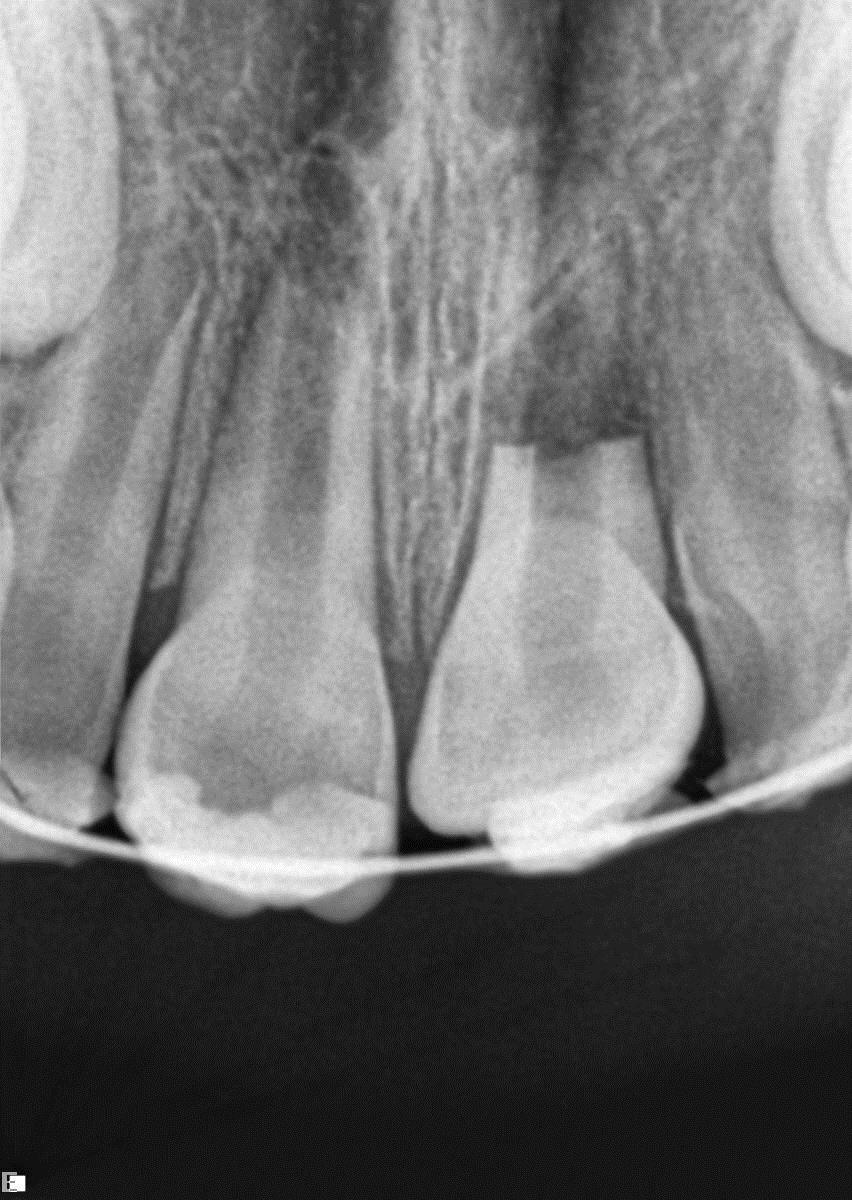

Elly was an active 8-year-old girl; while she and a friend were cartwheeling on Christmas day, she was struck in the mouth by the other girl’s foot. Elly’s upper-right central incisor was avulsed, and the upper left central incisor was palatally luxated (with mid-root horizontal root fracture). Elly’s father placed the avulsed tooth into milk immediately and went directly to her dentist. The dentist replaced the avulsed 11 into its socket and attempted to reposition the 21, but the procedure was unsuccessful. Four days later, Elly presented for assessment.

Fig 1

FIG1